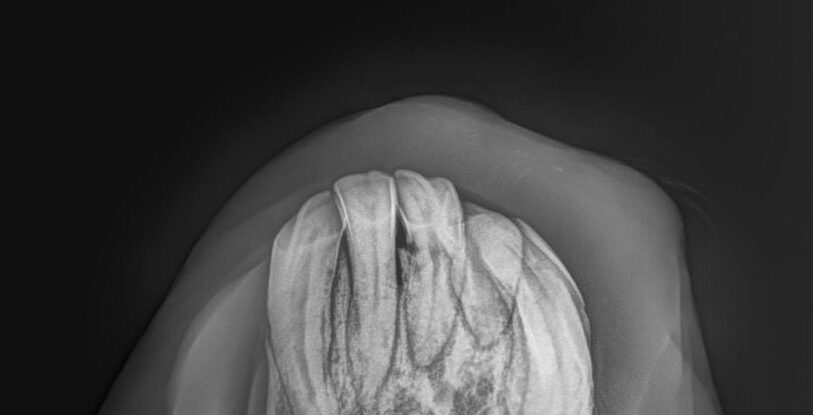

- röntgenologische Untersuchung zur Bestätigung der Verdachtsdiagnose EOTRH

- deutliche Befunde erkennbar

- resorptive und hyperzementotische Veränderungen an den Schneidezähnen/Schneidezahnwurzeln